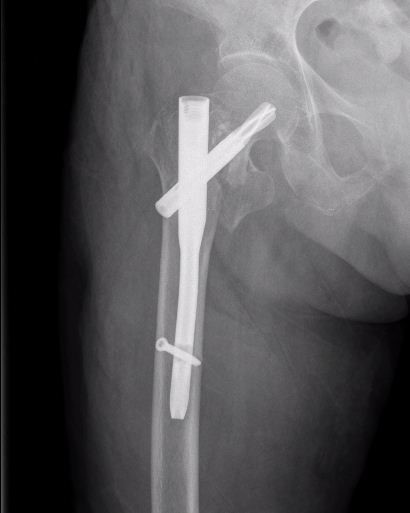

5月7日一早,在手术室、麻醉科、心内科、ICU等科室和病区护理团队的密切配合下,吴韦主任对患者施行了骨折闭合复位内固定手术治疗,仅通过两个2-3cm左右的小切口就顺利完成手术操作,手术用时仅1小时,术中出血不到100ml。